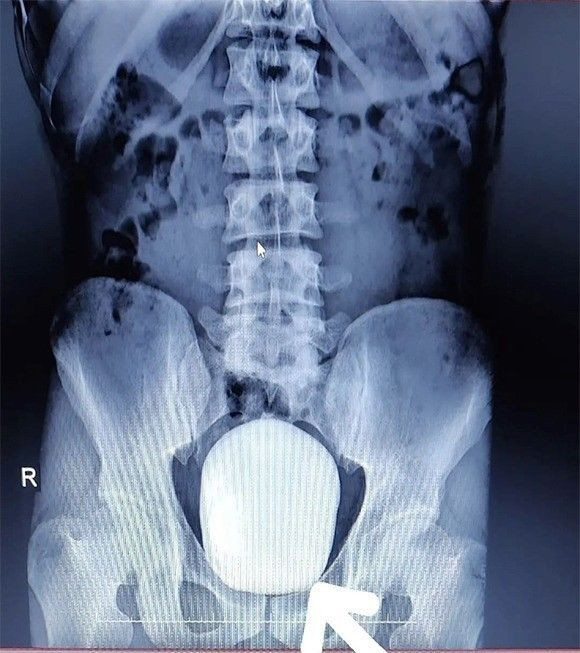

KARAMAN'da 27 yaşındaki gencin mesanesinden 1 kilo ağırlığında iki adet taş çıkarıldı.

Çekilen röntgeninde hastanın mesanesinde 2 adet büyük çapta taş tespit edildi.

Doç. Dr. Güven Erbay ve Dr. Öğretim Üyesi Ahmet Şanlı tarafından yapılan cerrahi operasyonla hastanın mesanesindeki 2 taş başarılı bir şekilde alındı.

"Devasa bir taşı gördük"

Başarılı geçen ameliyatla ilgili değerlendirmelerde bulunan Doç. Dr. Güven Erbay, “Hastanemize idrarda yanma şikayeti ile başvurdu. Yapılan tetkik ve görüntüleme sonucunda mesanesinde devasa bir taş olduğu gördük. Bunun üzerine ameliyat kararı aldık ve açık ameliyatla bu taşı aldık." dedi.